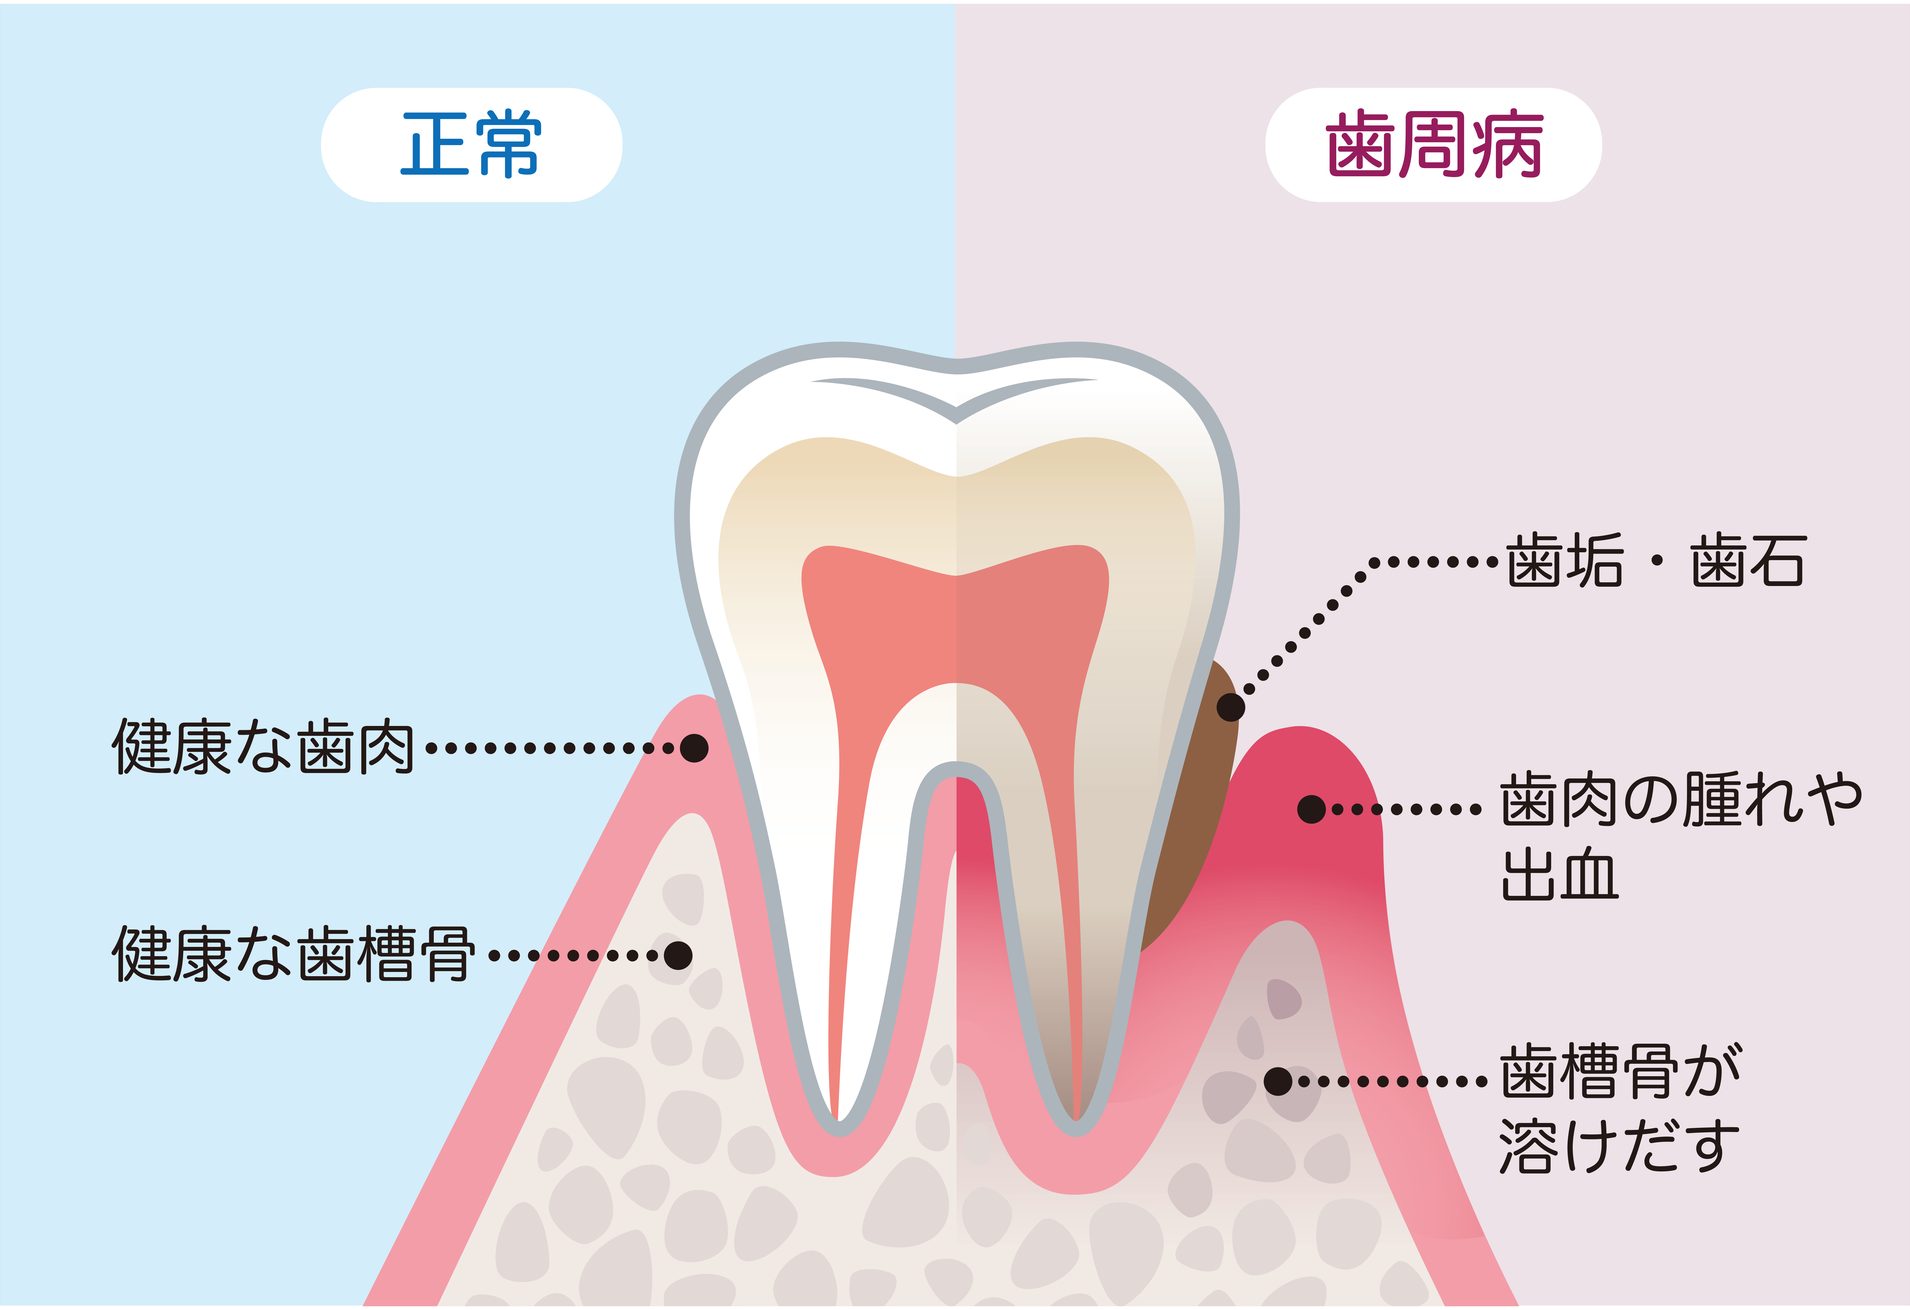

- 歯周病とは何か:基本的な理解

歯周病になると、歯茎が下がったり顎の骨が破壊されたりして、歯が揺れるようになります。その結果、抜歯を余儀なくされて歯を失う恐れがあります。

歯周病とは何か:基本的な理解

歯周病は、歯を支える組織が炎症を起こす病気です。細菌の増殖が引き金となり、歯肉や歯を支える骨に損傷をもたらします。最初の症状は炎症を伴う軽度の歯肉病から始まりますが、放置すると骨を破壊し、最終的には歯の喪失につながる可能性があります。

歯周病の発生過程

歯石は歯肉に刺激を与え、歯肉が赤く腫れる状態、すなわち歯肉病を引き起こします。進行:そのまま放置すると、炎症は歯周ポケットに広がり、骨を含む歯を支える組織を破壊します。これが歯周病です。

歯周病の影響

歯の喪失

歯周病が進行し、歯を支える骨が溶けると、最終的には歯がぐらつき、抜け落ちることがあります。